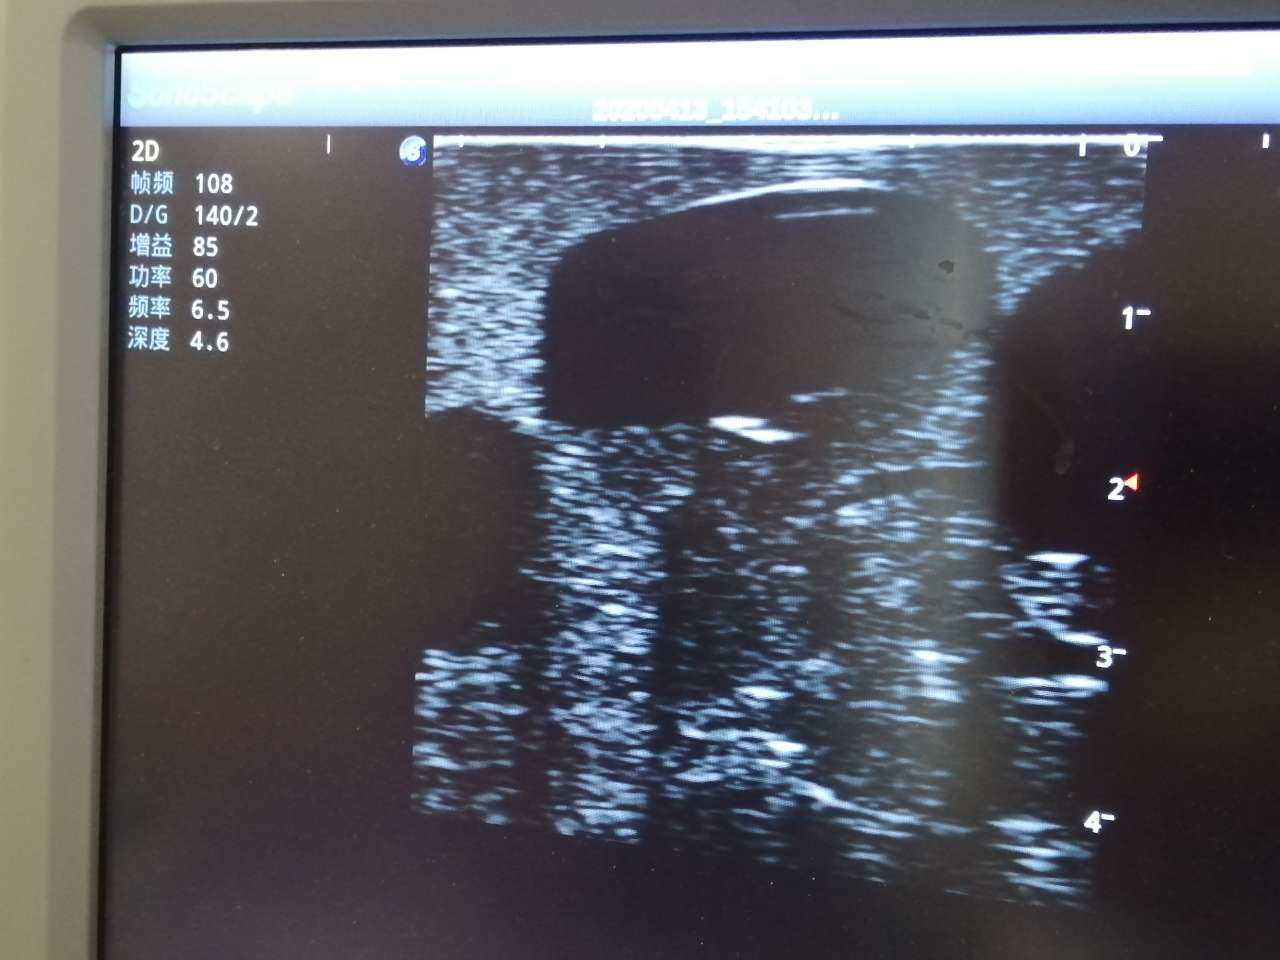

Abscess Drainage Ultrasound Trainer

Model TYE1562

Product size(mm)268×240×92

Outline

The trainer is designed for abscess ultrasound recognition, drainage, surgical cutting & suturing. With realistic landmarks and high-quality images, it’s an excellent choice for abscess-related skill training and practice.

Skills Gained

· Proper transducer positioning

· Ultrasound image interpretation

· Ultrasound recognition of abscess

· Abscess drainage

Features

· Anatomy: accurate anatomical structures like iliac crest, cleft starting point etc.

· Different abscess types: single sac on the right side and multiple sacs on the left side

· Durable material, easy to carry

· Realistic abscess feel and touch

· Compatible with various real ultrasound machines

· High-quality ultrasound images to show skin, soft tissues, abscess cavity and pus

· Support abscess incision, drainage with visible fluid and suturing